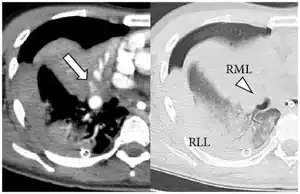

| Extravasation of contrast medium in right middle lobe and compression of middle lobe bronchus by a pulmonary hematoma | |